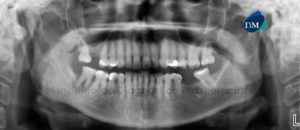

Paciente masculino, 17 años de edad, es referido al Instituto de Diagnóstico Maxilofacial (IDM) para evaluación tomográfica de premolar retenido. En la radiografía panorámica (Figura